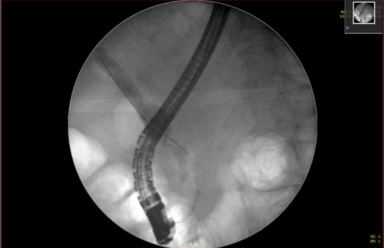

A magnetic resonance chloangiopancreatography (MRCP) demonstrated a dilated CBD of 15mm diameter with 13mm filling defect indicating obstructive gallstones. Intrahepatic ducts showed biliary strictures, which may suggest primary sclerosing cholangitis (PSC), and irregular liver contours indicating chronic liver disease. A fibroscan result was 14kPA, consistent with liver cirrhosis. An endoscopic retrograde cholangiopancreatography (ERCP) with sphincterotomy and stenting was performed for removal of the gallstones. It also demonstrated a normal appearance of the biliary ducts with no suspicious areas hence biopsies were not performed. A second ERCP followed for stent and further gallstone removal. Unfortunately the patient’s symptoms did not improve. A subsequent abdominal USS demonstrated a persistently dilated CBD, unchanged in appearance from the previous scans.

Figure1, Figure2, Figure 5

Figure 1

Figure 2